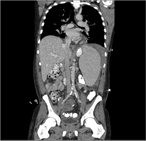

Primary extrahepatic bile duct neuroendocrine tumor with obstructive jaundice masquerading as a Klatskin tumor

Lauren Hoepfner and Jared A. White

Journal of Surgical Case Reports, Volume 2017, Issue 6, June 2017, rjx104, https://doi.org/10.1093/jscr/rjx104